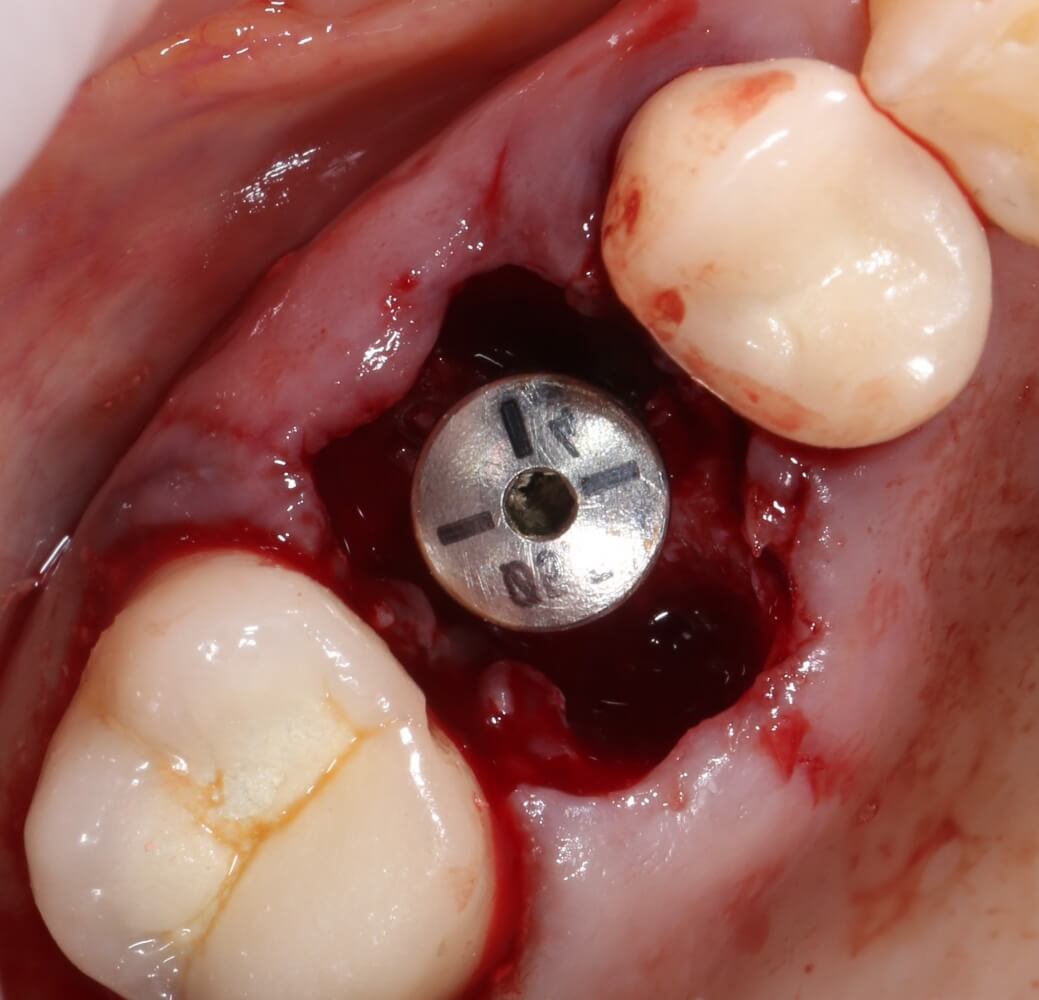

Почему всё это должен знать имплантолог? Дело в том, что суммарная длина конструкции «имплантат-абатмент-коронка» должна оставаться неизменной, если мы хотим, чтобы коронка была в прикусе и нормально функционировала. Это значит, что небольшая длина импланта должна быть компенсирована раздутым эго и большим джипом увеличением размеров супраструктуры, а именно — абатмента и коронки:

Хотя изобретатель имплантов Bicon, профессор Винсент Морган утверждает, что супраструктура может превышать длину импланта в пять раз:

Другими словами, нагрузка в 30 Н, приложенная к коронке в точке А, в точке B , будет равняться 90 Н, при условии, что соотношение имплантат/супраструктура будет как 1:3:

И, может быть, имплантату на это пофиг, остеоинтеграция позволяет и не такое. Но как насчет соединения имплантат-абатмент? Особенно, при отсутствии антиротационных элементов и соединяющих винтов на имплантах Bicon? Уверен, по этому поводу тоже есть какое-то научное исследование и, скорее всего, оно тоже утверждает, что «усё нормуль», но, опять же, Архимед…. физика…. простая механика… Извините, но как-то это не укладывается у меня в голове.